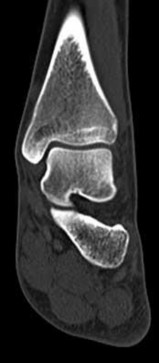

A 30-year-old female sustains a midfoot injury after falling from a horse. Radiographs demonstrate diastasis between the bases of the 1st and 2nd metatarsals. In a normal anatomic state, the native Lisfranc ligament originates and inserts on which two bony structures?

Explanation

The Lisfranc ligament is a stout, obliquely oriented intra-articular ligament that acts as the primary stabilizer of the second tarsometatarsal joint complex. It connects the lateral aspect of the medial cuneiform to the medial aspect of the base of the second metatarsal. Importantly, there is no direct ligamentous connection between the bases of the first and second metatarsals.